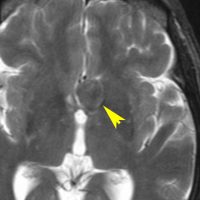

鞍上槽に強い石灰化を伴う腫瘍があります。視交叉左側から左視索が腫瘍化した,視路毛様細胞性星細胞腫です。右側のガドリニウム増強では一部に増強所見がみられます。施設によっては,頭蓋咽頭腫と間違えられ生検術をされるかもしれません。経過観察のみをします。

左が2016年,右が2023年のものです。7年間で全く腫瘍サイズに変化はありません。小さな腫瘍のう胞も石灰化も不変でした。